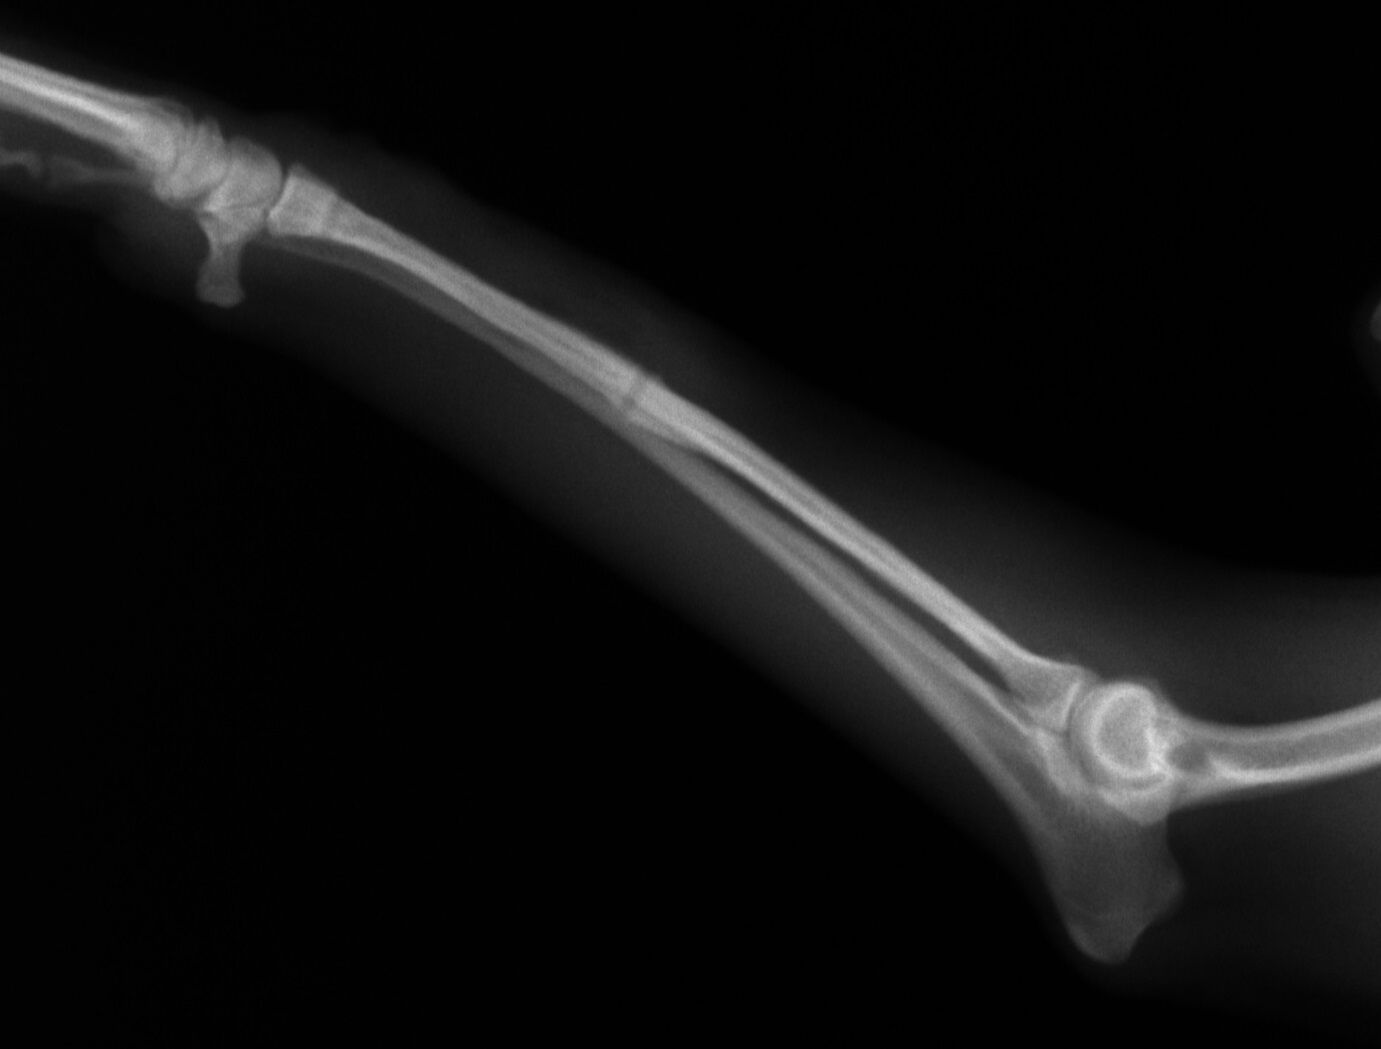

治療はプレートで固定する方法を行いました。骨折位置が橈骨先端に比較的近い位置だったことと、トイ・プードルは骨の増生が悪いことで有名なので少し気を遣う症例でした。プレートはステンレスプレートを用いました。手術直後が下の写真です。